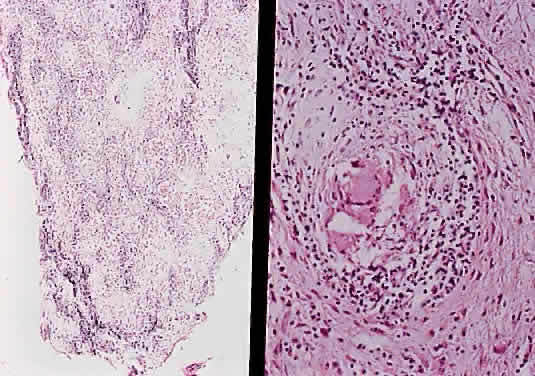

The optic nerve is affected in some manner in 1% to 5% of patients with sarcoidosis and is the second most frequently involved cranial nerve—the facial nerve being the most common.67,68 Rarely, sarcoidosis may present as tumefactive enlargement of the optic nerve without evidence of systemic disease. Most cases are misdiagnosed initially as meningioma or orbital pseudotumor (Figs. 50 and 51).67,69

Fig. 50. Bilateral thickening of the optic nerve and sheaths due to sarcoidosis. Computed tomography.

Fig. 51. Sarcoidosis of the optic nerve. Noncaseating granulomas replace the optic nerve parenchyma (low power, left; high power, right).